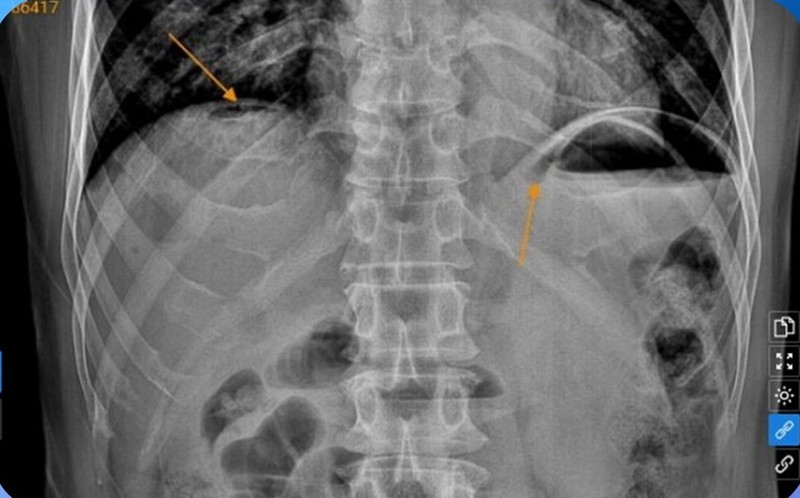

Bệnh nhân được chỉ định một số xét nghiệm cận lâm sàng, chẩn đoán hình ảnh phục vụ chẩn đoán. Kết quả xét nghiệm máu trong giới hạn bình thường, đặc biệt chụp X-quang ổ bụng không chuẩn bị phát hiện hình ảnh liềm hơi dưới vòm hoành 2 bên và hình ảnh siêu âm ổ bụng tổng quát cho thấy dấu hiệu rèm cửa vùng thượng vị. Đây là hai dấu hiệu kinh điển trong trường hợp thủng tạng rỗng.

Chụp X-quang phát hiện bệnh nhân thủng tạng. Ảnh BVCC